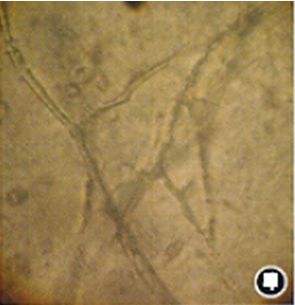

病例活检组织中可见大量粗大、无节、呈直角分枝的毛霉菌菌丝。

图片

光镜下可见粗大、无节、呈直角分枝的菌丝。